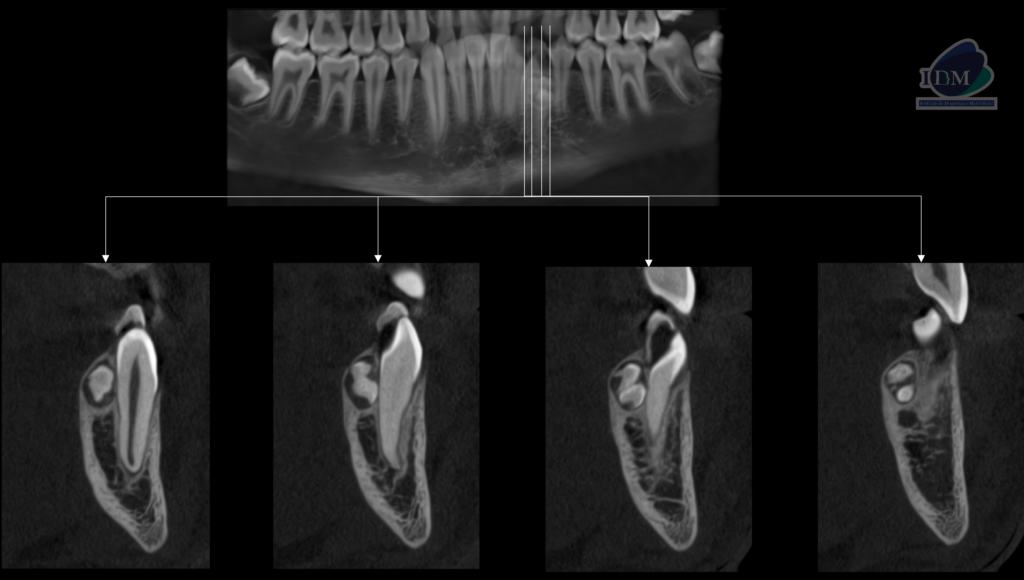

A la evaluación de la tomografía volumétrica (cone beam) en los cortes axiales (Figura 2) y transaxiales (Figura 3) se observa múltiples dentículos por lingual de la pieza 33, rodeado por un halo isodenso, de dimensiones 8,30 mm x 8,70 mm x 5,40 mm aproximadamente, que ocasiona el adelgazamiento de la tabla ósea lingual y la pérdida de la lámina dura lingual de la pieza 32.

En la reconstrucción 3D se representa la bifurcación radicular de pieza 33 (Figura 4).

CORTES TRANSAXIALES